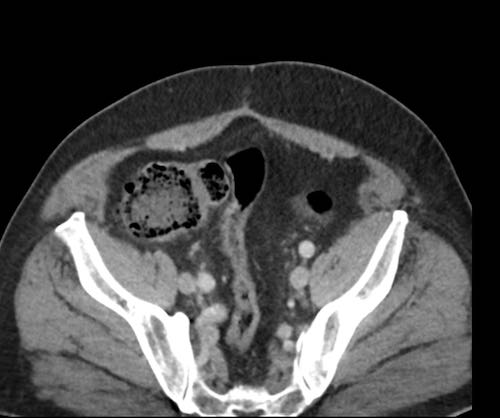

Cuộn xem ảnh CT

Ca lâm sàng 1

Cuộn qua các lát cắt.

Bạn có thể phát hiện tất cả các tổn thương cấy ghép phúc mạc không?

Bệnh nhân này đã được phẫu thuật và toàn bộ phúc mạc được ghi nhận phủ kín bởi các tổn thương u dạng kê.